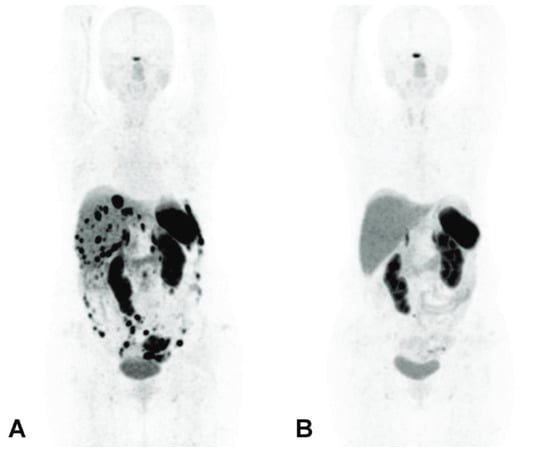

- Zhang, J.; Kulkarni, H.R.; Baum, R.P. Peptide Receptor Radionuclide Therapy Using 225Ac-DOTATOC Achieves Partial Remission in a Patient with Progressive Neuroendocrine Liver Metastases after Repeated β-Emitter Peptide Receptor Radionuclide Therapy. Clin. Nucl. Med. 2020, 45, 241–243. [Google Scholar] [CrossRef]

- Alan Selçuk, N.; Demirci, E.; Ocak, M.; Toklu, T.; Ergen, S.; Kabasakal, L. Almost Complete Response with a Single Administration 225Ac-DOTATATE in a Patient with a Metastatic Neuroendocrine Tumor of Unknown Primary. Mirt 2022, 31, 139–141. [Google Scholar] [CrossRef]

- Satapathy, S.; Sood, A.; Das, C.K.; Kavanal, A.J.; Mittal, B.R. Alpha Before Beta: Exceptional Response to First-Line 225Ac-DOTATATE in a Patient of Metastatic Neuroendocrine Tumor with Extensive Skeletal Involvement. Clin. Nucl. Med. 2022, 47, e156–e157. [Google Scholar] [CrossRef] [PubMed]